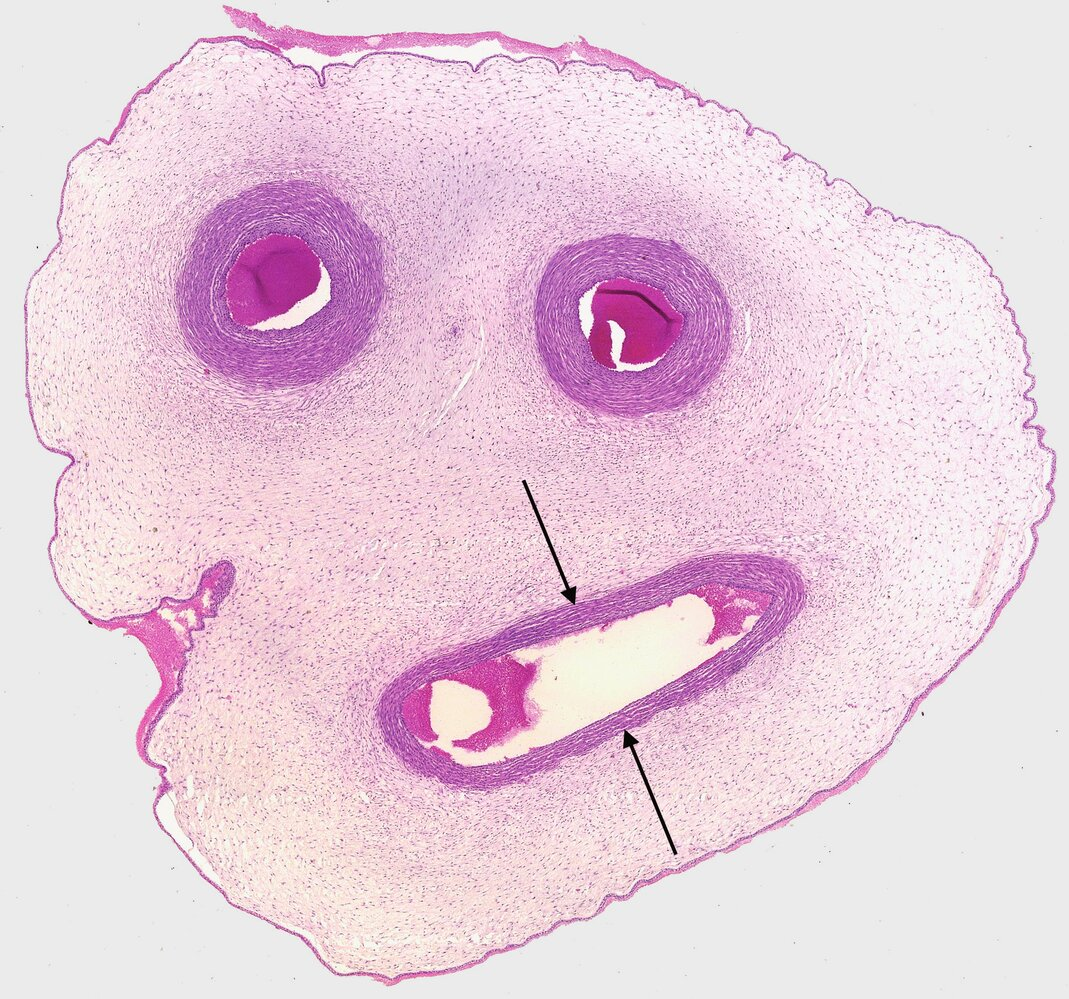

3. The image shows a cross-section of the umbilical cord.

In which of the following structures in an adult human can a remnant of the structure marked by arrows be found?

A. Ligamentum teres hepatis (Round ligament of the liver)

B. Ligamentum teres uteri (Round ligament of the uterus)

C. Plica umbilicalis lateralis (Lateral umbilical fold)

D. Plica umbilicalis medialis (Medial umbilical fold)

E. Plica umbilicalis mediana (Median umbilical fold)